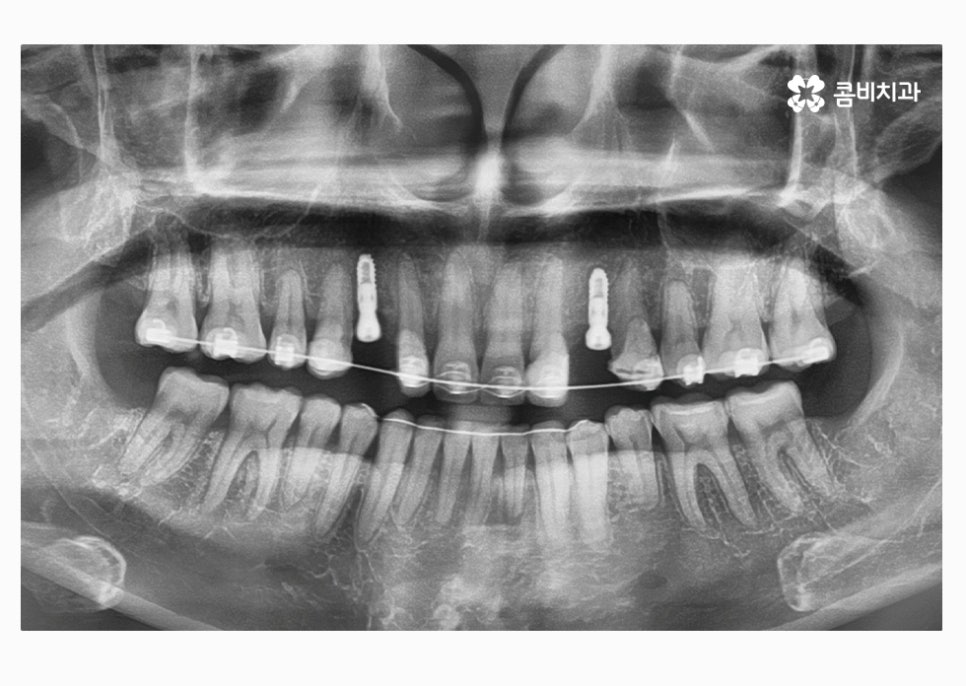

위에 표시된 치아는 이미 발치가 된 상태에서 임시치아를

부착하고 생활을 하셨던 환자이며 고르지 못한 치열을

개선하고 임시치아를 부착한 치아에 임플란트를 식립한 사례라고 할 수 있어요.

자세히 보시면 임시치아라는 것을 알 수 있고 엑스레이

사진을 보면 더 자세히 알 수 있습니다.

치아교정으로 치열을 가지런하게 하고

30대임플란트 식립까지 잘 마친 상태이며

식립 후에는 골 유착이 튼튼하게 이뤄지는지 기다린 후

주변 치아의 색과 모양에 맞는 보철물을 결합하여

마무리가 된다고 할 수 있어요.